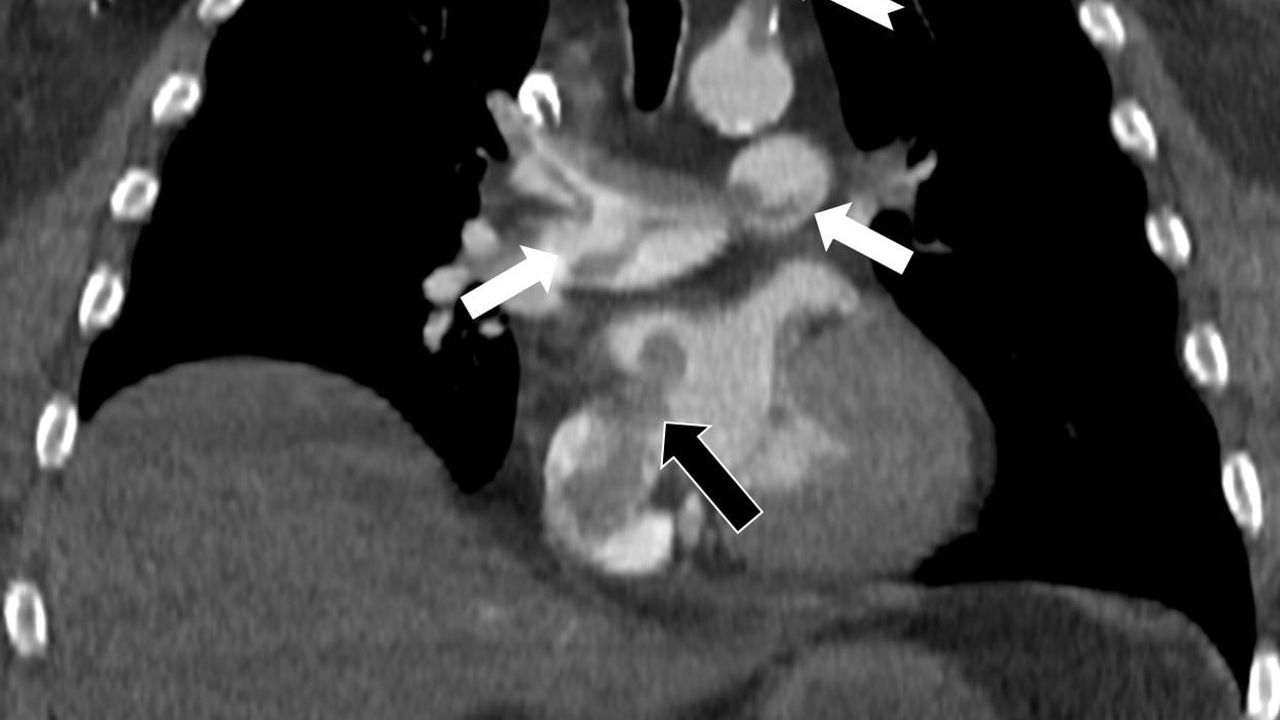

Çalışmada bilgisayarlı tomografi anjiyografisi görüntüleri, toplar damarlardan kaynaklanan pıhtının akciğer damarlarını tıkadığını ortaya koyarken; aynı zamanda kalp odacıkları arasındaki bir delikten geçen pıhtının kalbin sağ tarafından soluna geçip ana atardamara ulaştığını ve sol kol damarını tıkadığı gösterildi.